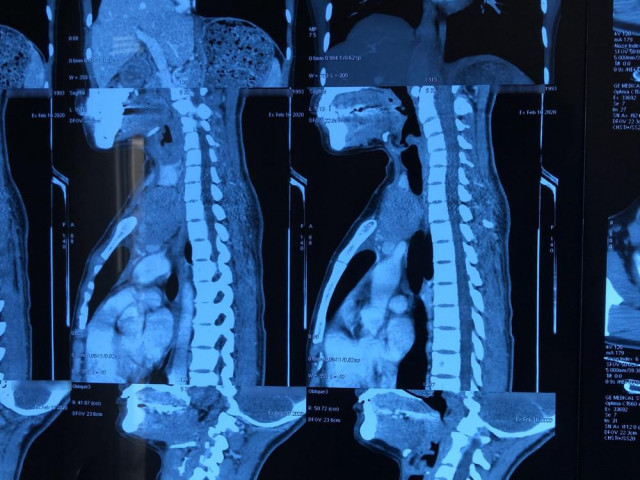

Ngày 16/12, thông tin từ Bệnh viện Sản Nhi Nghệ An cho biết, các bác sĩ của bệnh viện này vừa phẫu thuật nội soi lấy chiếc vòng tránh thai đâm thủng trực tràng một người phụ nữ 36 tuổi.

Qua quá trình thăm khám và hội chẩn, các bác sĩ xác định dụng cụ tử cung của chị N. đã bị lạc chỗ vào trong ổ bụng, phía thành sau tử cung. Chiếc vòng tránh thai đã đi lạc chỗ ra ngoài thành sau tử cung, thân vòng đâm thủng trực tràng, gây ổ áp xe tại chỗ.

Ca phẫu thuật diễn ra hết sức căng thẳng, bởi ngoài mục đích lấy vòng tránh thai, ekip còn nỗ lực hạn chế tối đa tổn thương đến trực tràng cho bệnh nhân. Các bác sĩ phải mất 2 giờ để hoàn thành ca phẫu thuật này.